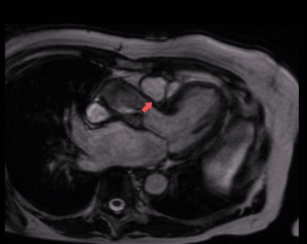

Assessing aortic stenosis with the help of cardiac MRI (CMR) 10th Oct 2017 - Andrew R. Houghton, MD Learn how to assess aortic stenosis with the help of CMR. Taken from our Cardiac MRI Essentials ...